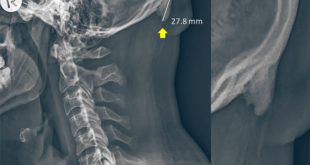

Read More »Study: Young People are Developing ‘Hornlike Spikes’ at Back of Their Skull Due to Poor Posture

Aberrant postures have led to an increase in young adults developing a bone growth at the back of the skull, according to a study by University of the Sunshine Coast scientists. A radiograph of a 28-year-old male participant. Image credit: Shahar Sayers, doi: 10.1038/s41598-018-21625-1. In 2016, University of the Sunshine …